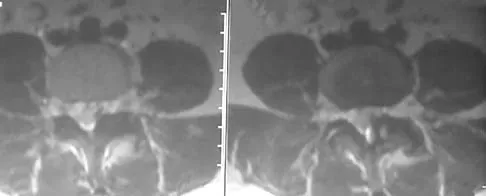

A 58-year-old man with type 1 diabetes mellitus is seen in the emergency department and he reports a 3-day history of a red swollen foot but no history of trauma. Examination reveals that the skin is intact, and the patient has discomfort with passive range of motion at the ankle, hindfoot, and midfoot joints. He denies any fever. Laboratory studies show a WBC count of 7,800/mm3, an erythrocyte sedimentation rate of 40 mm/h, a C-reactive protein level of 23, and a serum glucose of 100. A radiograph and MRI scans are shown in Figures 16a through 16c. What is the next most appropriate step in management?

Explanation